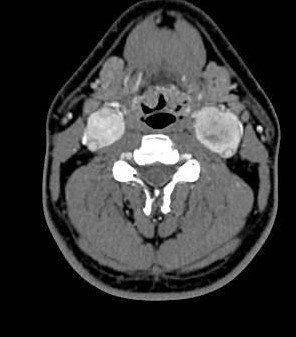

Masculino, 42 anos, Lesões expansivas nas bifurcações carotídeas.

Paraganglioma Carotídeo.

Os paragangliomas (tumores glômicos, glomus) são lesões originarias das células parangaglionicas da crista neural. São tumores pouco frequentes, benignos, de crescimento lento e extremamente vascularizamos. Suas principais localizações no espaço carotídeo são: na bifurcação carotídea, em torno do gânglio do nervo vago, junto a base do crânio, no bulbo jugular e comprometendo simultaneamente a orelha média e bulbo jugular.

• TC: Lesão de partes moles mal delimitada e ricamente vascularizara, com destruição permeativa das estruturas ósseas adjacentes, apresentando realce intenso no exame contrastado.

• RM: Sinal intermediário nas sequências ponderadas em T1 e hipersinal nas imagens ponderadas em T2, observando-se frequentemente imagens serpinginosas de ausência de sinal dentro da lesão em todas as sequências de imagem, característica da presença de vasos dominantes, associados a focos hemorrágicos, intratumoral, representados por focos de alto sinal (aspecto de sal e pimenta - identificação de vasos calibrosos no interior do tumor). O uso do contraste paramagnético evidencia sua hipervascularização.